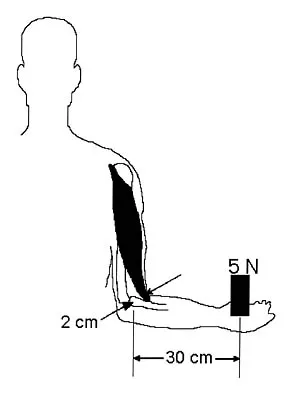

Figure 2 shows the radiograph of a 26-year-old auto mechanic who injured his right dominant elbow in a fall during a motocross race. Examination reveals pain and catching that limits his range of motion to 45 degrees of supination and 20 degrees of pronation. The interosseous space and distal radioulnar joint are stable. Management should consist of